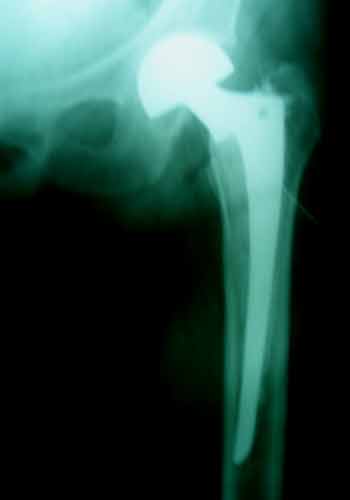

Case:10 Pathological Fracture

Seconderies from CA Prostate in 65 years old male patient treated with cemented bipolar prosthesis.

Pre-op

Post-op X-ray